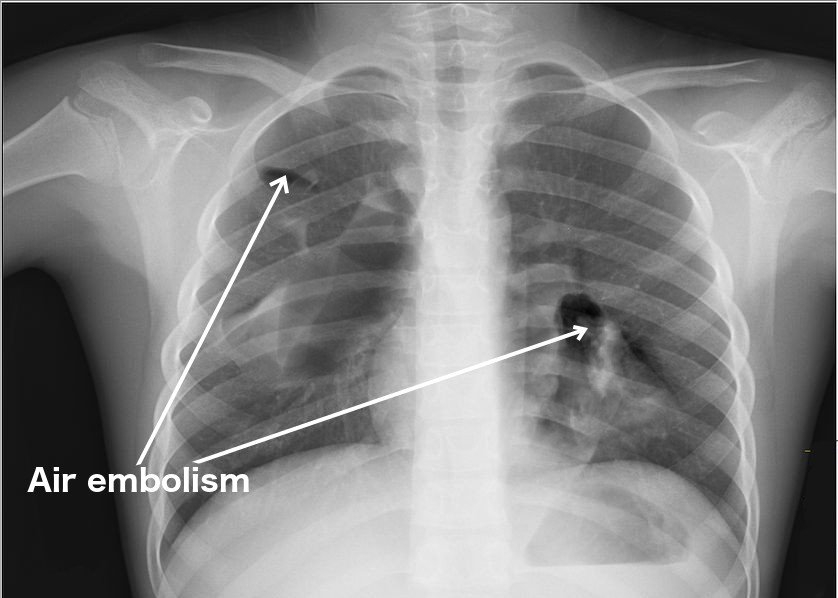

Air embolism in human body x ray sonography

(Photo Credit :Nevit Dilmen / Wikimedia Commons)

Similarly, depending on the size of the blood vessels and the air bubble, the effects would vary. Not all our blood vessels are the same size. Some vessels, like capillaries, have a very thin diameter, just large enough for one line of cells to pass through. On the other hand, some of them are much wider, like the aorta.